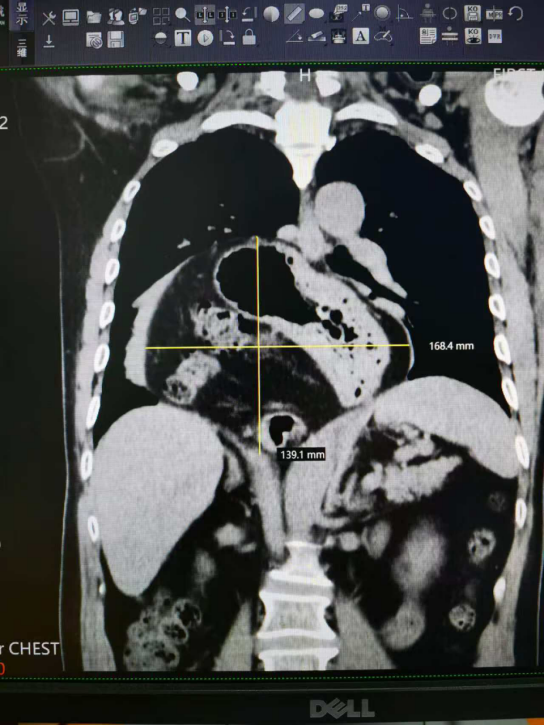

CT提示胃及部分肠管疝入胸腔,大小约16.8cmx13.9cm